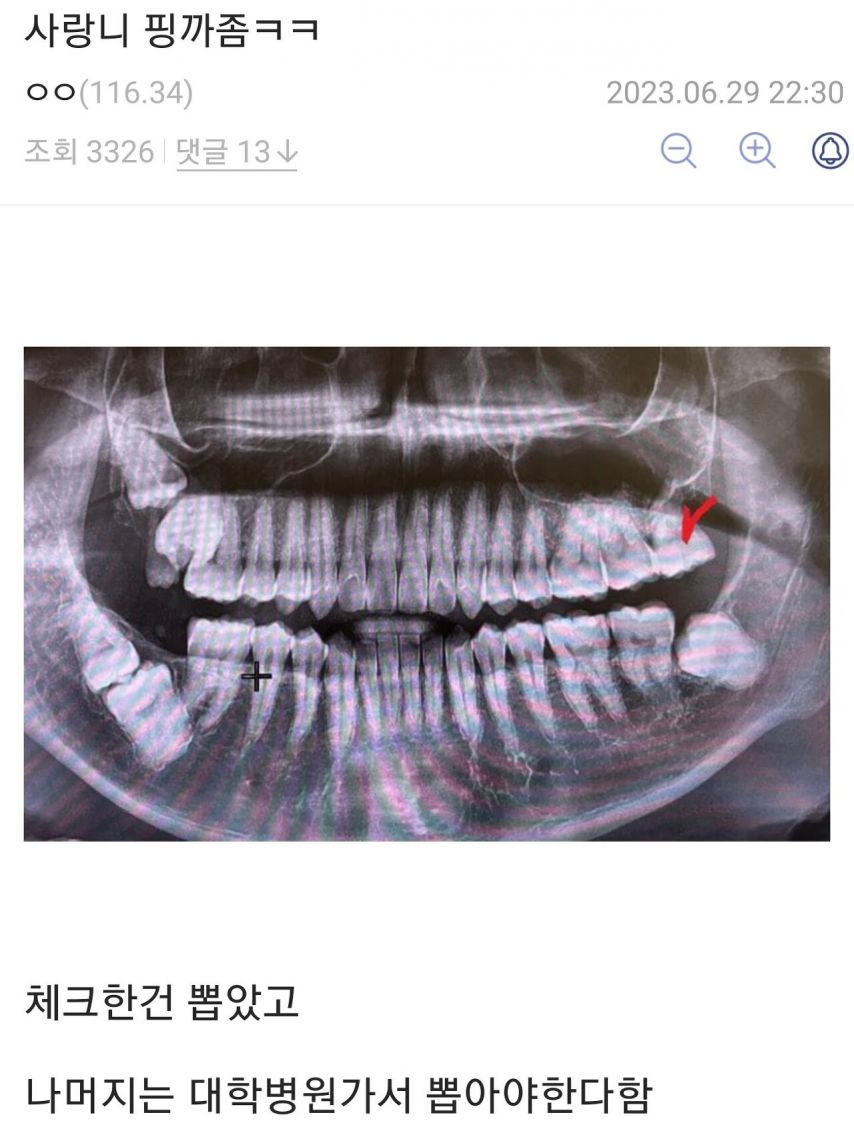

사랑니 평가

달천